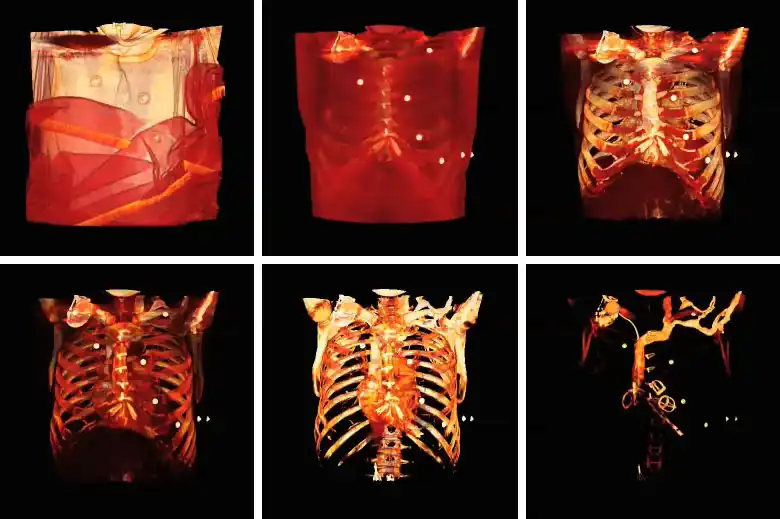

A final feature to note about volume rendering is that 3D editing techniques can be applied so as to exclude unwanted features from the computations and to expose internal structure. This is illustrated in the following figure, where planes of an orthogonal frame can be moved to crop the voxel data from six directions.